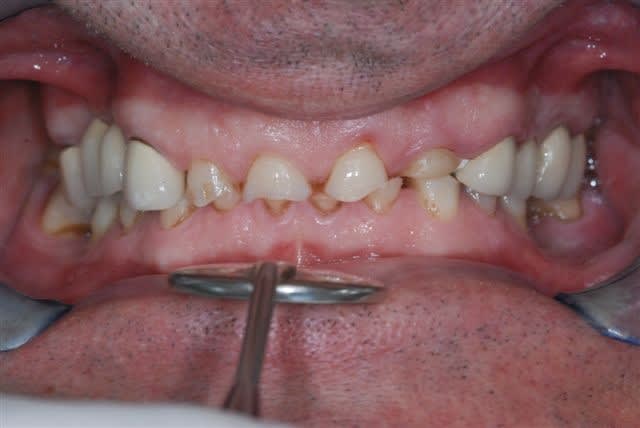

Ci-joint les photos d'un patiente qui s'est présentée pour refaire les angles cassés sur 11 et 12.

Les dents sont vitales, pas d'antécédents de choc ou de tics et manies pouvant expliquer le phénomène.

Elle a consulté un ortho qui lui a dit que ce n'était pas de son ressort et je n'en suis pas si certain.

Les molaires sont en partie en inocclusion, en particulier les 15-16/45/46, et légèrement côté G. Pas de douleur à l'ATM.

Elle a bénéficié d'un traitement ODF pendant l'adolescence pour tenter de corriger une tendance à la classe III squelettique. Il y a un terrain familial à la Cl III (encore plus marquée chez le frêre). Les dénudations radiculaires au maxillaire en sont certainement une séquelle (ainsi qu'un brossage intempestif) du traitement.

Sur les photos, on remarque ce qui ressemble à une asymétrie de la branche horizontale de la mandibule, qui se traduit par l'articulé inversé côté droit.

Moi j'aurais envie de retablir une protection canine. Les latéralités ont l'air de se faire sur les incisives, normal que ça casse. Elle a dû faire une petite chute de ski quand même,ou prendre un coup de boule sur la mandibule qui a provoqué une fissure et puis le morceau est parti plus tard.